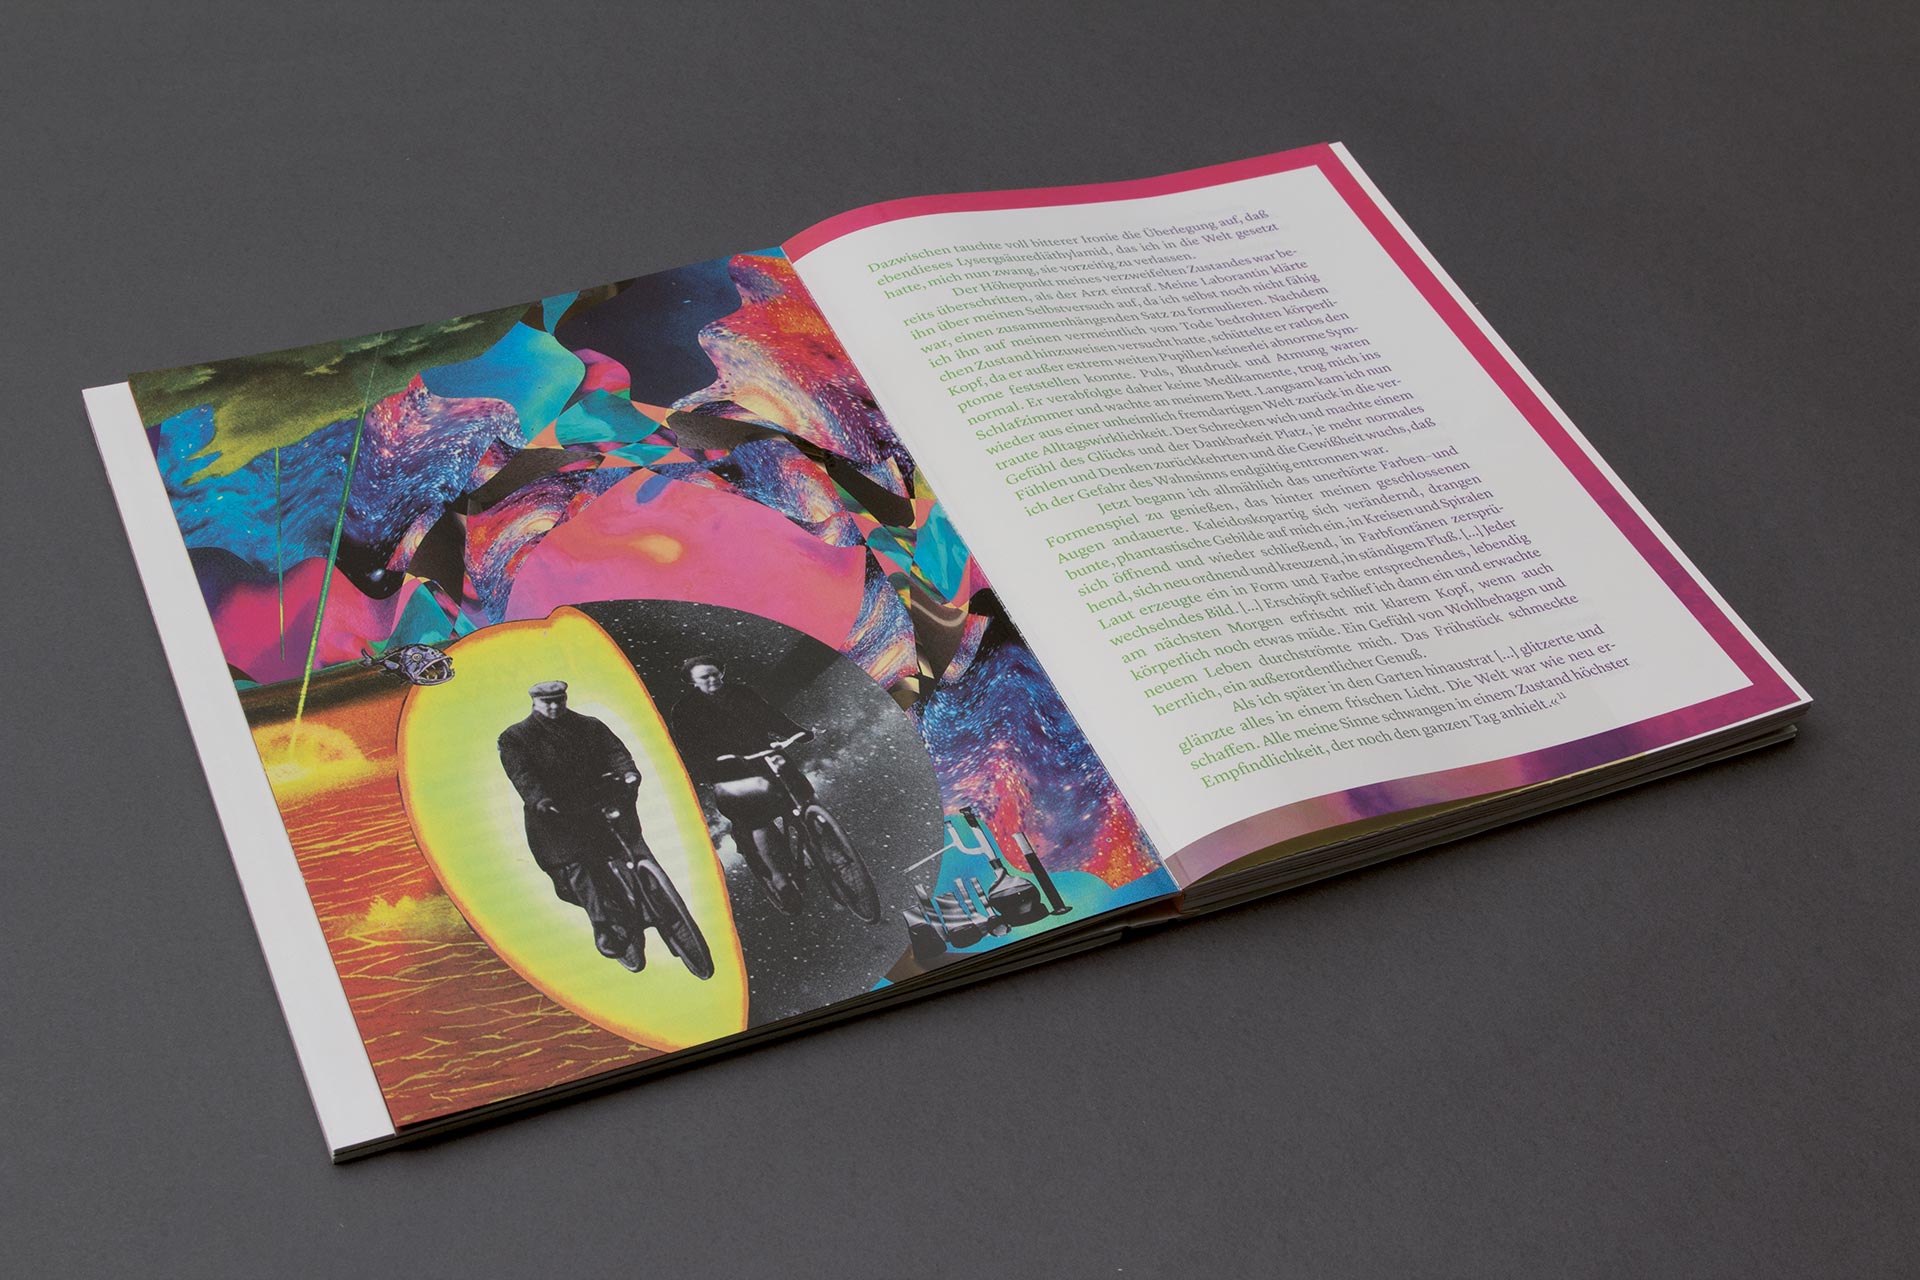

Follow The White Rabbit

ID # 23816

Fachhochschule Mainz, DE

professor : Isabel Naegele

Sara Ellinger

contact :

www.saraellinger.de